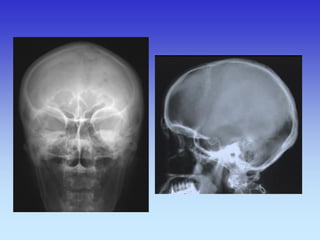

KOSTI GLAVE

Kosti lubanje – rtg.

PROFILNA SNIMKA GLAVE

LUBANJA Baza 1. Parijetalna kost 2. Lambdoidna sutura 3. Foramen magnum 4. Petrozni dio temporalne kosti 5. Mandibula 6. Mastoidne stanice